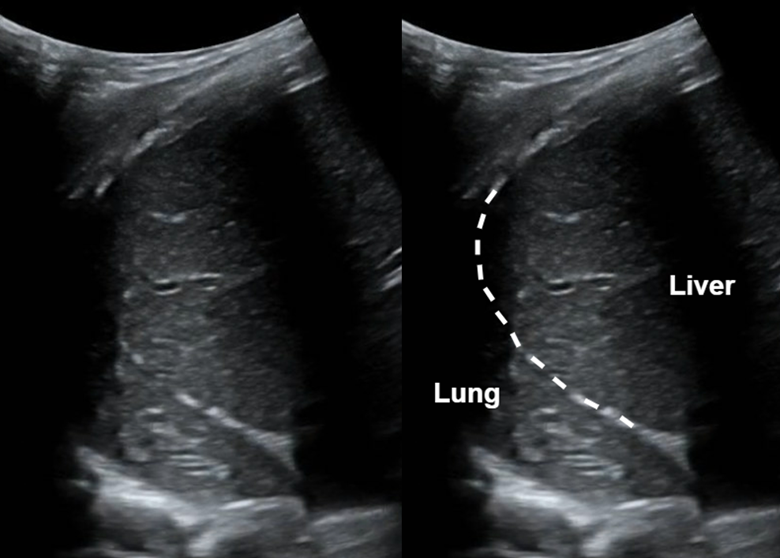

Shown above is the right hemidiaphragm or right upper quadrant view. We can see the liver and lung with the diaphragm (dotted line) in between. Note that the lung looks very similar in appearance to the liver! This liver-like appearance of the lung is called ‘hepatization’.

In the image above the lung contains small, dark linear structures that are called air bronchograms. They represent air-filled bronchi.

·       This patient had a combination of both lung atelectasis and pneumonia. Typically, lung tissue is not visible on ultrasound considering that it is normally filled with air. However, in the case of pneumonia, alveoli are filled with inflammatory fluid creating consolidations, while in the case of atelectasis the alveoli are collapsed rather than fluid filled. This pathologic lung tissue is now visible with ultrasound!

·       Lung consolidations change the appearance of lung tissue on ultrasound such that its echogenicity looks remarkably liver-like, termed ‘hepatization’. This can also be seen in atelectasis.

·       Air bronchograms visible on ultrasound represent air trapped within the small bronchi which are surrounded by lung tissue. Static air bronchograms are mostly seen in compression atelectasis but can also be seen in pneumonia; they are hyperechoic air-filled bronchi that do not move with respirations. Dynamic air bronchograms are pathognomonic for pneumonia; they represent air bubbles moving through fluid filled lung tissue. On ultrasound, dynamic air bronchograms look like numerous hyperechoic opacities that move with respirations.